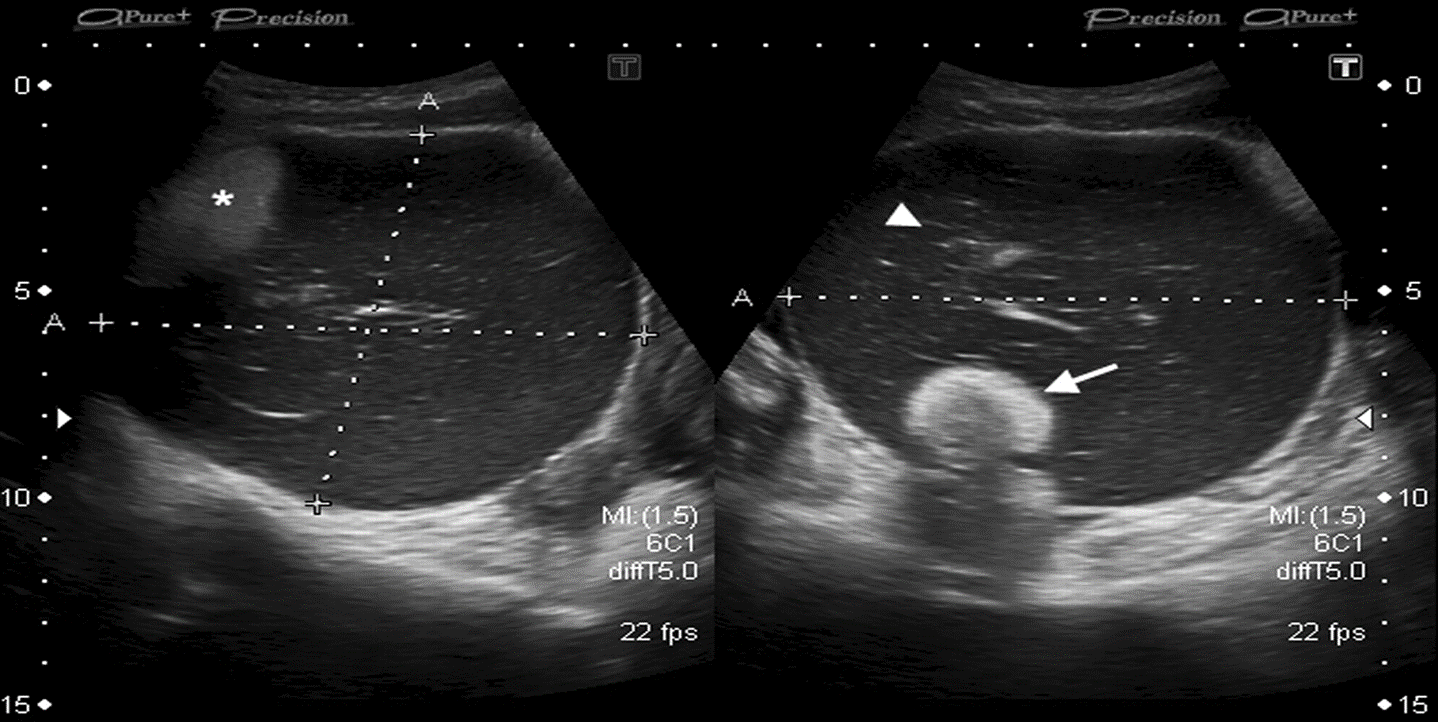

Dermoid cyst/mature cystic teratoma Ultrasound appearance

- Large tumor with a solid component

- Solid component arises from the wall of the cyst.

- Small areas of calcification